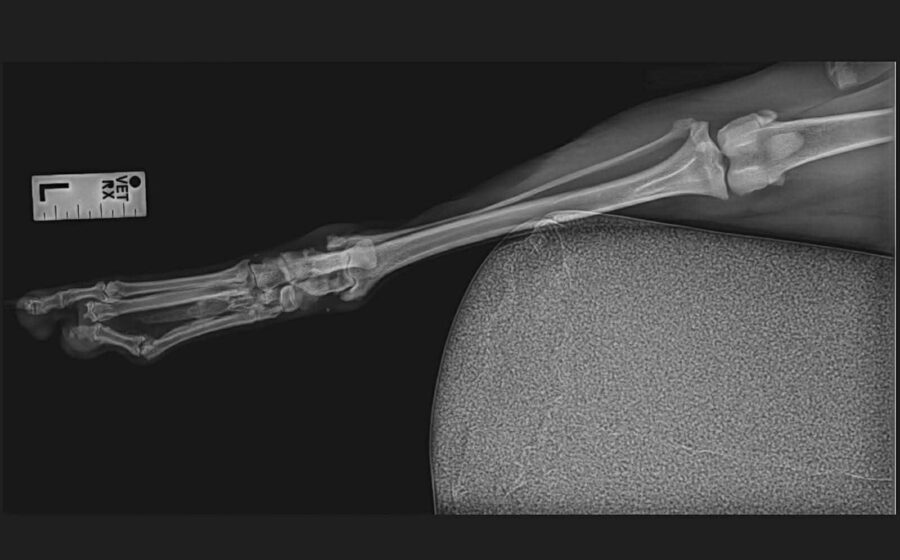

Inura ist eine wunderschöne junge Husky-Hündin, die trotz schwerer Vergangenheit eine beeindruckende Stärke und Sanftmut in sich trägt. Sie wurde an Bahngleisen gefunden – verletzt, verängstigt und ganz allein. Ein Zug hatte ihr mehrere Zehen am Hinterbein abgetrennt. Dank eines aufmerksamen Mannes kam sie sofort in tierärztliche Behandlung und konnte gerettet werden. Ihre Pfote ist inzwischen gut verheilt, doch die fehlenden Zehen werden für immer bleiben.

Aktuell humpelt sie und belastet das Bein nur begrenzt. Unsere Tierärztin geht davon aus, dass Inura ihr Leben lang humpeln wird. Das ist nicht dramatisch für sie, aber es bedeutet, dass sie besondere Unterstützung verdient. Eine Orthese – also eine speziell angepasste Stütze – könnte ihr künftig hervorragend helfen. Sie würde den Druck auf die empfindliche Pfote reduzieren, den Kontakt zum Boden abfedern und ihr das Laufen erleichtern, besonders auf härteren Untergründen. Mit etwas Muskelaufbau, sicheren Böden und dieser zusätzlichen Unterstützung kann Inura sich gut und stabil durchs Leben bewegen.